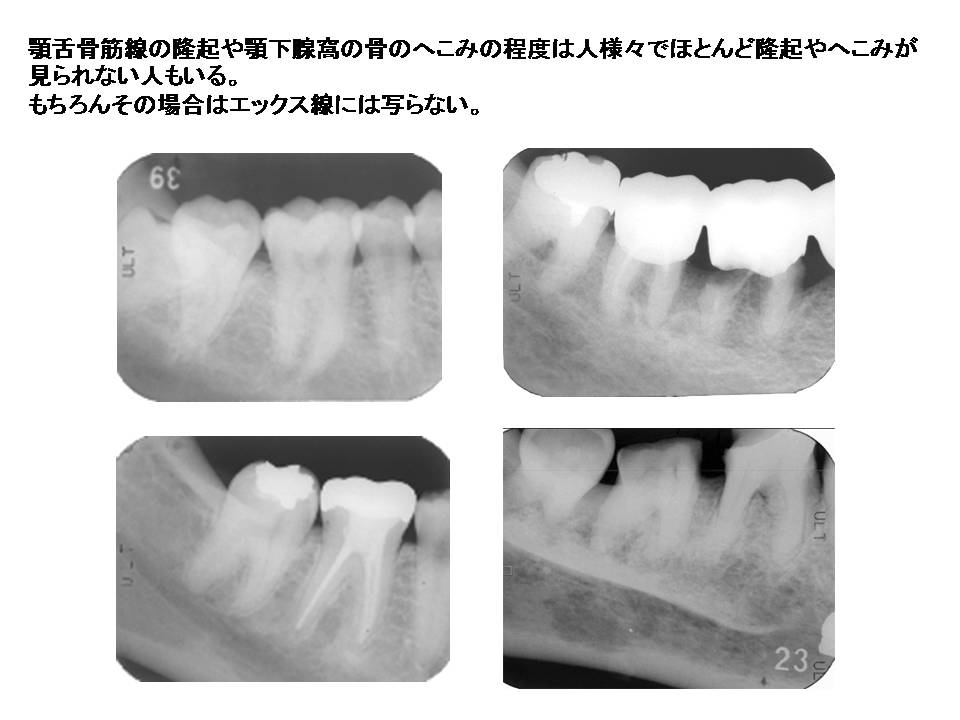

口内法(二等分法・咬合法)撮影の解剖